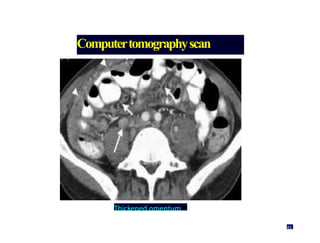

Computertomographyscan

Thickened omentum

45